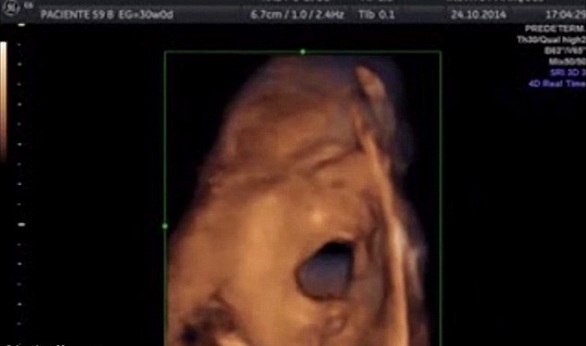

بالفيديو والصور.. الأجنة تغني في الرحم منذ الأسبوع 16

كشفت دراسة إسبانية حديثة أن الأجنة يمكنها الغناء وأن تسمع جيدا منذ الأسبوع 16.

ولأول مرة، تمكن علماء في معهد ماركيز ببرشلونة من إظهار أن الجنين يمكن تحديد الأصوات بل أنهم يردون باستخدام أفواههم وحنجرتهم.

وأشارت الدراسة إلى أن أذن الجنين يكتمل نموها في الأسبوع 16 من الحمل.

وقبل هذه الدراسة، كان العلماء يعتقدون أن الجنين لا يستطيع السمع قبل الأسبوع 18، وأنه يستطيع السمع بشكل واضح في الأسبوع 26.

وشارات نساء في فترة الحمل من 16 أسبوعا إلى 38 في الدراسة التي وجدت أن 87% من الأجنة يردون على أجهزة الصوت المثبتة على بطون أمهاتهم.

وأظهرت الصور أن الأجنة يحركون أفواههم كما لو أنهم يحاولون الغناء.